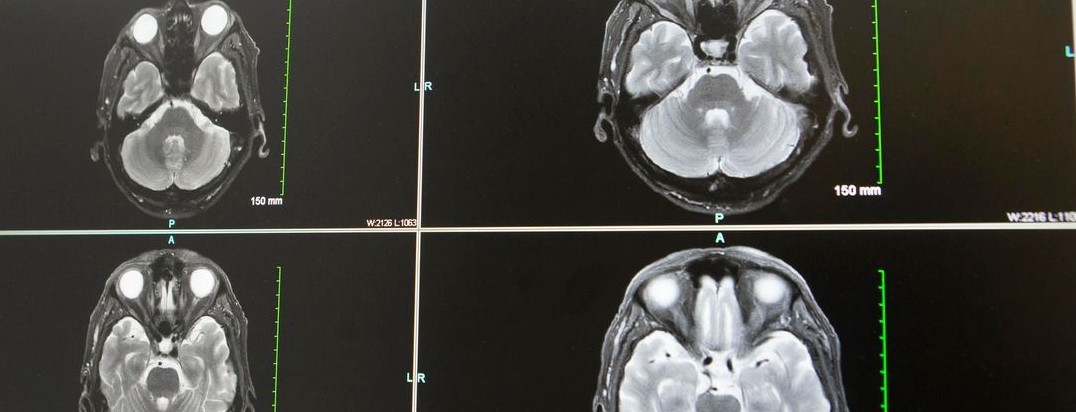

Featured photo at top of brain scans. Photo courtesy of Joseph Broderick.